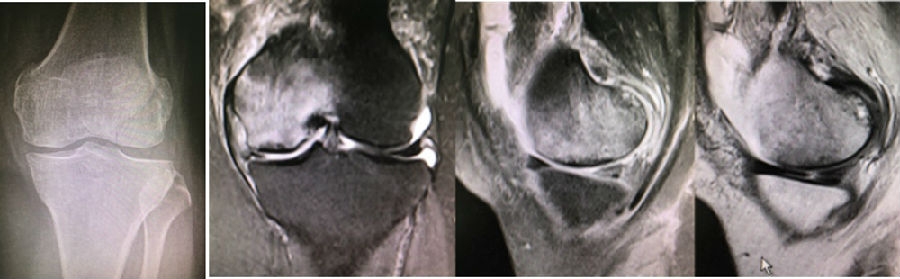

病例2:女,69岁,主诉左膝关节内侧疼痛1月余。2017年11月X光见右膝股骨髁负重区的软骨下区域出现了椭圆形透亮影,MR检查见股骨内侧髁骨坏死,合并内侧半月板外突和后角层裂,半月板相对突出百分比(RPE)25.32%,矢状位病变区域前后径为23.96mm,关节线会聚角6°。

予克氏针钻减压,消炎止痛药物口服、静滴唑来膦酸钠注射液,避免负重6周,后改部分负重至3个月,患者依从性差。2018年1月复查MR见骨髓水肿少许吸收,坏死区扩大,半月板相对突出百分比(RPE)33.53%,矢状位病变区域前后径为26.89mm,患者仍有膝关节疼痛症状,建议行手术治疗,患者拒绝手术后失访。